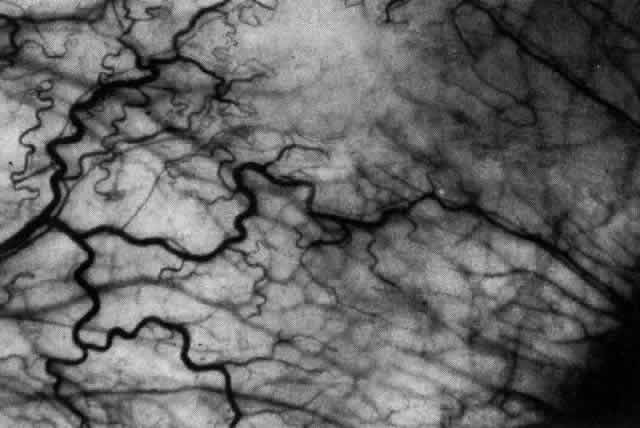

a result of changes in collagen and proteoglycan. The shape of the sclera is determined by the inner layer of the optic cup, the retina, and the choroid. The sclera is derived from a condensation of mesectoderm (from the neural crest). The sclera develops outside the choroid late in development, starting anteriorly. The development of sclera and choroid is in turn induced by the retinal pigment epithelium. Abnormalities of development at this stage may lead to colobomas and in lesser instances to progressive myopia. Development of sclera over the posterior pole is not complete until the end of the fifth month of fetal life.2 From then on, the shape of the sclera is modified by the effect of the intraocular pressure. The elastic fibers in the sclera can be stretched beyond their limit of elasticity when not supported by a fully developed collagenous structure. The whole globe can therefore be distended until 3 years after birth; the lamina cribrosa is the only scleral structure that can be stretched after this age. Although the sclera has a low metabolic activity, it requires some nutrition, which it derives from the underlying choroid and overlying episclera, the sclera being entirely permeable to water, glucose, and proteins. The sclera transmits blood vessels but retains a very scant supply for its own use. However, the sclera is supplied with nerves, particularly in the anterior segment near the muscles; damage to these nerves in destructive scleritis is undoubtedly the major cause of pain in this condition. The nerves also appear to be stimulated by distention of the sclera. The episclera, or Tenon's capsule, provides for part of the nutrition of the sclera and for the cellular response to inflammation. In addition, the episclera also acts as a synovial membrane for smooth movement of the eye and, together with the muscular sheaths to which it is fused, provides a check on excessive movement. The episclera is a fibroelastic structure formed after the development of the sclera from a mesenchymal condensation of the areolar structures of the orbit, possibly in response to eye movement. A deep or visceral layer is closely applied to the sclera. The outer parietal layer combines with the muscle sheaths, fusing first with the visceral layer and then with conjunctiva near the limbus. The subconjunctival space is traversed by only a few fibers, which form very little barrier to edema; it is not a lymphatic space because it contains no endothelium. The parietal layer of Tenon's capsule is penetrated by the muscles, anterior ciliary artery, veins, nerves, and aqueous veins. The two layers of the episclera are thinly joined together by connecting fibers, and each layer is supplied with its own vascular network derived from the anterior ciliary arteries. With the increasing use of anterior segment fluorescein angiography in the early detection of severe necrotizing disease of the sclera, it is necessary to have an understanding of the normal anatomy of the vasculature of the anterior segment of the eye.3–5 The blood supply to this region is enormous, being derived from the anterior ciliary arteries, but with extensive collateral arterial anastomoses to the posterior ciliary arteries at the root of the iris (Fig. 1). The anterior system is readily visible with the slit lamp and by anterior segment fluorescein angiography, especially if the eye is inflamed, and its recognition is of vital importance in the differentiation of episcleral and scleral conditions. The separation and displacement of these vascular layers give the most important clinical clues to the site and, hence, the severity of the inflammation. On slit lamp examination, three layers of vessels are readily visible. The conjunctival plexus, which is the most superficial layer of vessels, can be moved over the underlying structures. The superficial episcleral capillary plexus (Fig. 2) is a radially arranged series of vessels lying within the parietal layer of Tenon's capsule. The vessels in this layer anastomose at the limbus with the conjunctival vessels, with other members of the same plexus, and with the deep plexus. The deep episcleral capillary network (see Fig. 2) is closely applied to the sclera in the visceral layer of Tenon's capsule. The vessels anastomose freely with each other, forming a syncytium. The large vessels to and from the intrascleral plexus traverse the episclera near the insertions of the muscles. The conjunctival and superficial episcleral vessels can be blanched with 1:1000 epinephrine or 10% phenylephrine, but the deep vessels are affected slightly. This is of considerable assistance when attempting to differentiate deep and superficial inflammation.

The direction of flow, the distinction between arteries and veins, and the integrity of the circulation can be determined only by the use of anterior segment fluorescein angiography.4,5 |

ARTERIAL PHASE Anterior Episcleral Arterial Circle The anterior ciliary arteries run radially toward the limbus within Tenon's capsule, giving few, if any, branches until they reach the anterior part of the globe. Their positions are very variable, and they do not always follow the rectus muscles. They bifurcate 2 to 5 mm behind the limbus, and each division runs forward and circumferentially to anastomose with a branch from an adjacent artery. This results in an anterior episcleral arterial circle (Figs. 3 through 5). The divisions of the anterior ciliary arteries are typically superficial at their origins but run deeper at their anastomoses. They occasionally dip too deep to be seen in fluorescein angiograms (Fig. 6).

From the anterior episcleral arterial circle, four distinct circulations are supplied: episcleral, anterior conjunctival, limbal, and iris. Episcleral Circulation Immediately after their origin by bifurcation of the anterior ciliary arteries, the contributions to the anterior episcleral circle divide again to give recurrent branches that run posteriorly and subdivide to form a netlike episcleral plexus (see Fig. 5; Fig.7). The variability of the positioning of the anterior ciliary arteries inevitably leaves large areas of episclera far from such an arterial supply (see Figs. 4, 6, and 7). These areas receive other posterior branches from the episcleral circle. Where the circle runs deep within the sclera, such branches appear as isolated perforating vessels (see Fig. 6). They fill very shortly after the episcleral circle, and they also divide repeatedly as they run posteriorly.

Anterior Conjunctival Circulation Throughout their superficial course, the arteries of the episcleral circle give off fine loops that run forward into the limbal reflection of the conjunctiva before curving back radially and dividing to form the lacework of the anterior conjunctival capillary plexus (see Fig. 2). The delicate column of blood within the anterior conjunctival loops may be punctuated by a string of individual erythrocytes, suggesting that the lumen is approximately 12 μm in diameter. Anterior conjunctival loops may also arise from perforating posterior branches of the episcleral circle (see Fig. 6). The anterior conjunctival circulation, supplied by the anterior ciliary arteries, always fills before the posterior conjunctival circulation, which is derived from the posterior tarsal vessels (see Figs. 4 and 5). The watershed zone between these sources can fill very late (see Fig. 5). However, anterior conjunctival loops do sometimes anastomose with arteries of similar caliber derived from the posterior tarsal circulation. Limbal Arcades Limbal arcades are supplied by anterior branches from the episcleral circle. Their origins are often shared with those of the anterior conjunctival loops, and, where the circle runs deep, they too are derived from the perforating posterior branches. They often fill very late during a normal angiogram (see Fig. 7). The limbal capillary loops never leak fluorescein, even during high-dose angiograms, suggesting that their endothelial cells are united by tight junctions. Iris Vessels The first flush of fluorescein within the anterior episcleral arterial circle always coincides with filling of the radial arterioles of the iris. It may be implied from this that the iris receives a major supply from the anterior ciliary circulation (see Fig. 6). In some angiograms, the iris circulation appears to derive directly from the episcleral circle. This raises the possibility that the “major circle of the iris” and the episcleral arterial circle are less distinct entities than has hitherto been presumed. VENOUS PHASE Anterior ciliary veins accompany the arteries, but there is no well-organized venous ring corresponding to the anterior episcleral arterial circle. The posterior episcleral branches of the arterial circle are paralleled by centripetal venules, and looping anterior conjunctival venules are interspersed between the arterioles (see Figs. 4 and 5). The posterior conjunctiva drains back into the tarsal circulation. CAPILLARY PHASE The episcleral capillary net is often difficult to discern below the more prominent conjunctival circulation. It is most clearly seen when the conjunctival circulation fills late for anatomic or pathologic reasons. The anterior conjunctival capillary plexus forms an interlacing network between the anterior conjunctival arterioles. Perfusion of the watershed zone that separates the territories supplied by the anterior ciliary and posterior tarsal systems may be delayed by as much as 15 seconds after first flush (see Figs. 5 and 7). However, this region is often crossed by arteriolar anastomoses between the two circulations, and the destination of venous blood is irrespective of its origin from the anterior ciliary or posterior tarsal circulations. |